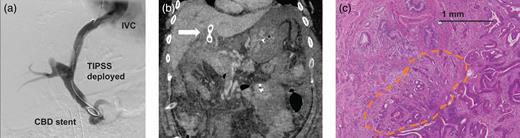

Hepatic vein wedge pressure measured 30 mmHg compared to an arterial pressure of 12 mmHg confirmed portal hypertension; however, a fibroscan revealed no evidence of cirrhosis. Prophylactic β-blockers were commenced. Liver histology from a percutaneous biopsy suggested congenital hepatic fibrosis (CHF) as a potential underlying cause of portal hypertension (Fig. 1c). Following intense multidisciplinary discussion, it was decided that in the context of a relatively young, cardiovascularly fit patient with non-cirrhotic liver disease, a TIPS procedure was appropriate, with a view to reconsidering surgery. A literature search failed to identify evidence to support a decision to adopt a staged TIPS with PD for a high-grade dysplastic lesion.

Significant residual biliary dilatation remained, which prompted placement of a 6-cm partially covered metal wall stent with subsequent improved drainage. A Viatorr® stent graft (10 mm, Gore) was then placed between the middle hepatic vein and left portal vein. Pre-TIPS pressures measured as 19 mmHg was reduced to 7 mmHg postprocedure; unfortunately, this initial TIPS failed requiring a second, successful procedure (Fig. 2a).

(a) Successful TIPPS deployment following insertion of a partially covered metallic biliary stent enabled portal decompression and resection to be performed. (b) Postoperative CT scan revealed failure of the TIPS (arrow) along with SMV thrombus resulting in significant venous congestion of the small bowel. (c) Histological examination of the resected specimen revealed a small cholangiocarcinoma.

The patient subsequently developed postoperative pancreatitis, complicated on postoperative day 4 by respiratory distress requiring intensive care unit admission. CT imaging revealed small fluid collections related to the pancreatic anastomosis, which were not amenable to drainage. Strikingly, repeat CT scan on postoperative day 6 demonstrated TIPS failure with extension of thrombus into the superior mesenteric vein (SMV) and significant small bowel venous congestion. Despite the ominous appearance (Fig. 2b) conservative management with broad-spectrum antibiotics, inotropic support and low molecular weight heparin resulted in gradual improvement with discharge home achieved on day 28. Final pathology unexpectedly revealed a 15-mm pT1pN0 distal cholangiocarcinoma with clear resection margins (Fig. 2c), for which no adjuvant therapy was required.